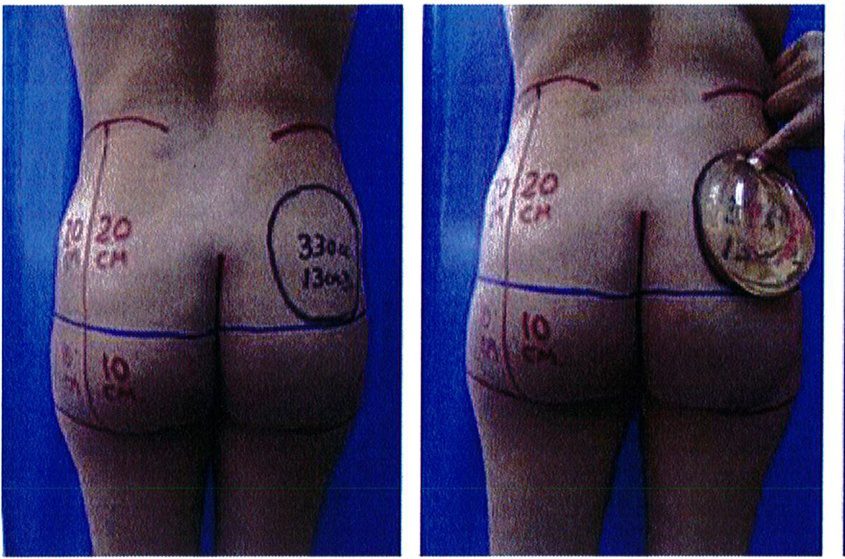

Để tránh tình trạng quá ngắn hoặc quá dài của vùng mông (hay còn gọi là mông dài/ngắn) thì tác giả đã kết hợp một phép đo đơn giản trước phẫu thuật, đo khoảng cách từ mào chậu phía sau tới đường ngang đi qua trung điểm nếp liên mông (khoảng cách A) và từ đường ngang đó tới nếp lằn mông (khoảng cách B) (Hình 1) đế tính vị trí chuẩn xác của khối im- plant.

Để tránh tình trạng phần mông trên được nâng lên quá mức, khoảng cách A thông thường phải gấp đôi khoảng B để có thể phù hợp cho nâng mông dưới cơ.

Nếu khoảng cách A ngắn hơn, nên sử dụng mặt phẳng trong cơ để tạo điều kiện cho khối im- plant được đẩy xuống thấp hơn 1 chút, giúp đạt được kết quả thẩm mỹ lý tưởng.

Hình. 1. Đánh giá trước phẫu thuật để lựa chọn bệnh nhân với mặt phẳng im- plant phù hợp.